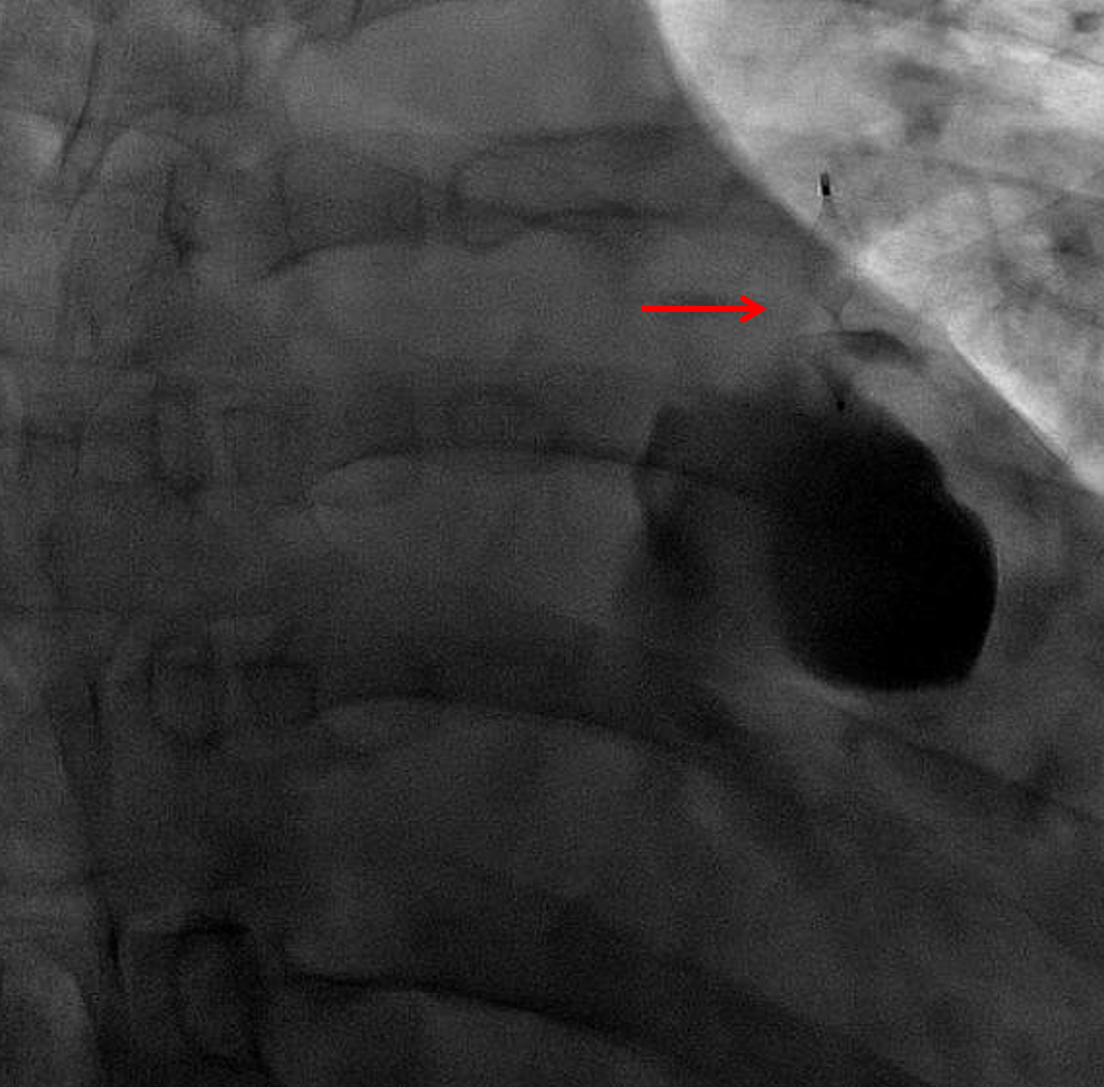

Sample ReportFindings concerning for necrotizing pneumonia in the left lower lobe with a large associated pulmonary arterial pseudoaneurysm. Recommend conventional pulmonary arteriogram and possible endovascular coiling.